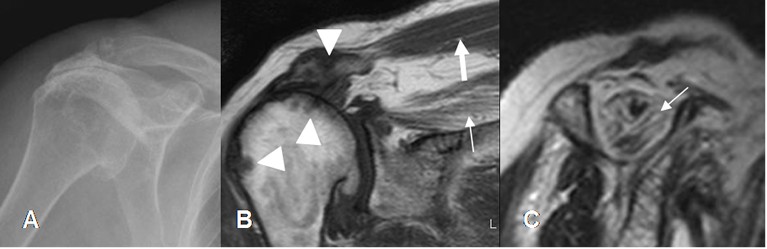

Fig 113. Alteración en la señal del supraespinoso.

A, B, C y D: RM coronal en T2. Distintos hallazgos patológicos, en el tendón del supraespinoso. Grado 0: Tendón normal en A. Grado 1: Tendinitis en B. Grado 2: Ruptura parcial en C y Grado 3: Ruptura completa en D.